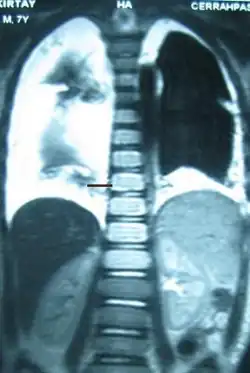

The cisterna chyli can be found in a thoracic MRI, making it possible to confirm chylothorax. However, MRI is not the ideal method to scan the thorax, and so it is rarely used. Another diagnostic technique is conventional lymphangiography. It is rarely used since there are equally sensitive yet less invasive techniques available to identify a chylothorax. Lymphangiography procedures use the contrast dye agent lipiodol, which is injected into the lymphatic vessels. The chylothorax shows up on the images and identifies the source any leak in the thoracic duct.[1]